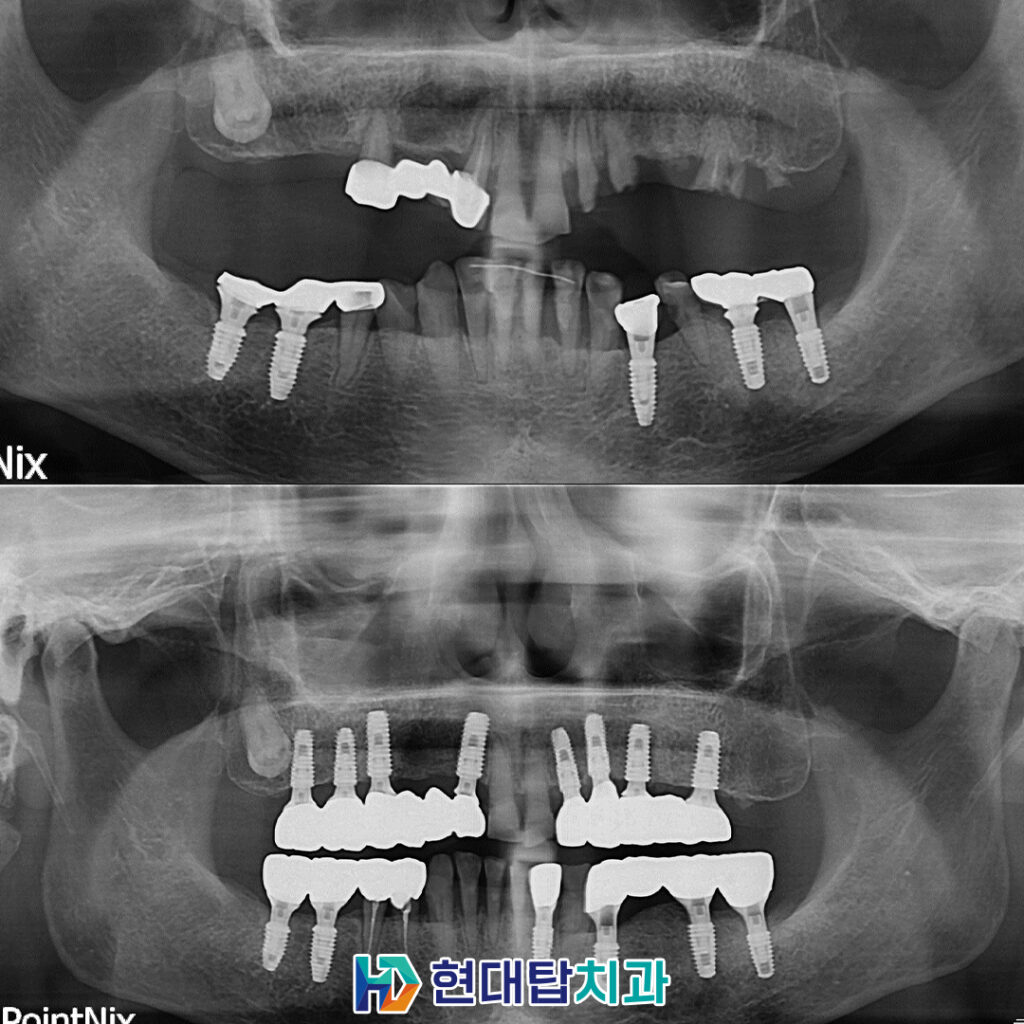

환자분께서는 오른쪽 위 어금니

부위는 이미 상실한 상태였고,

왼쪽 위는 앞니를 제외하고

남아 있는 치아들은 치아머리가

부러져 뿌리만 남아 있는 상태였습니다.

하여 살려서 사용할 수 없는

왼쪽 위의 치아 뿌리들을 모두

발치하고, 오른쪽에 남아 있던 브릿지까지

모두 발치한 후 치아 상실 부위에

임플란트 식립 계획을 수립하였습니다.

오른쪽 아래 기존 임플란트의

보철물을 위쪽 임플란트와 잘

맞도록 수정하여 보다 안정적인

교합을 가질 수 있도록 하였습니다.